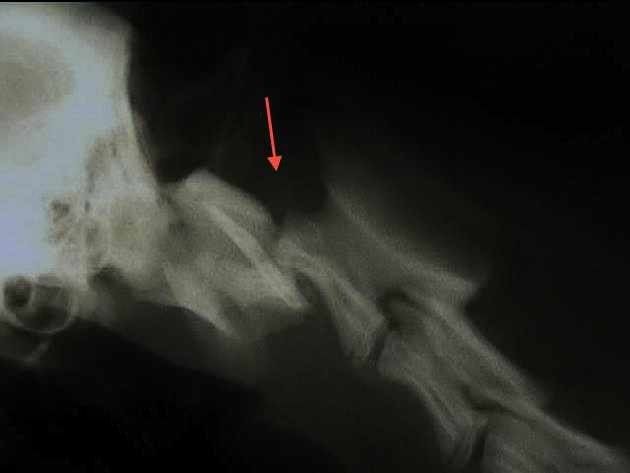

Radiographie des membres:

Pour la recherche de fractures mais également l’évaluation de différents problèmes articulaires comme l’arthrose ou la dysplasie.

Fracture du fémur et du bassin chez un chat